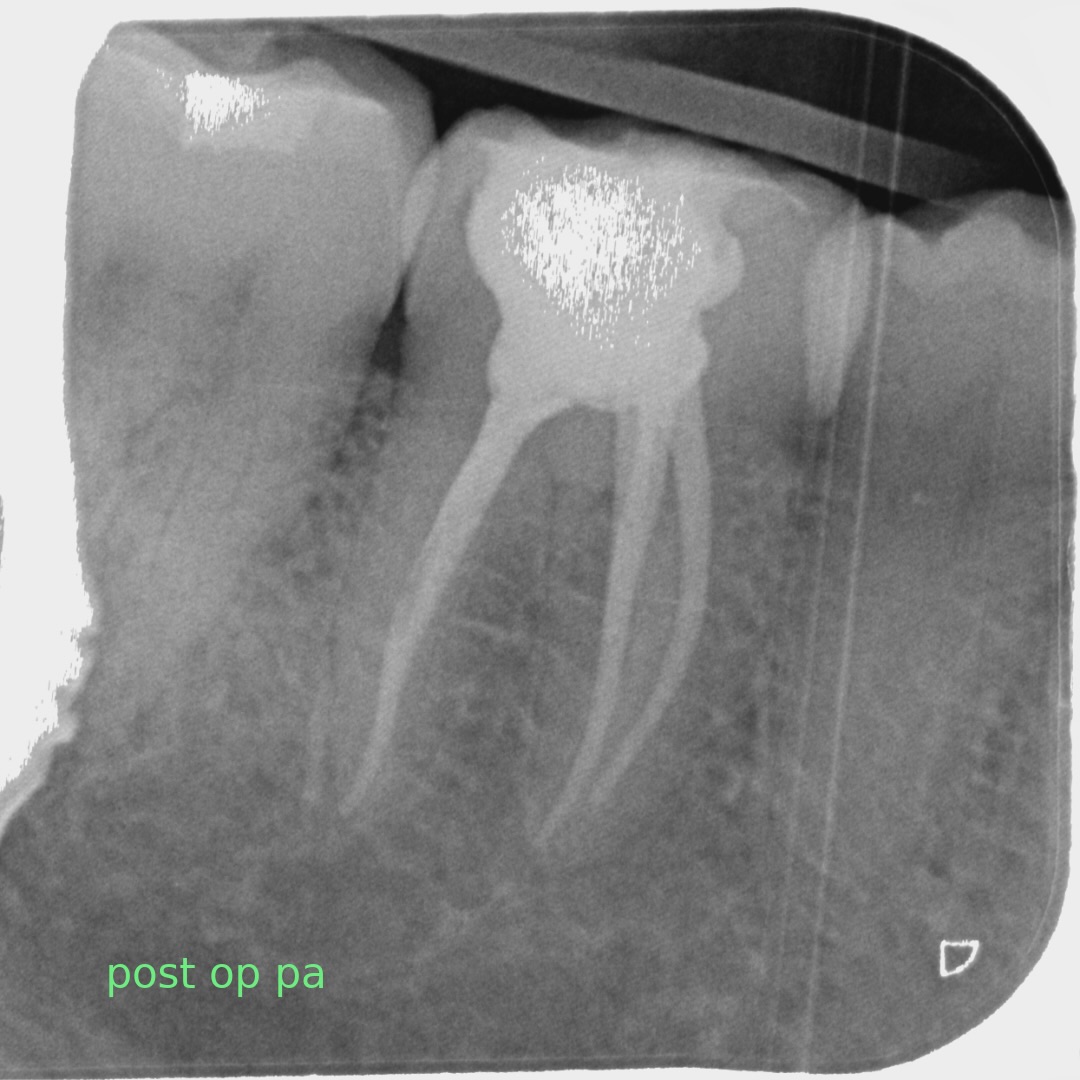

A comprehensive, non-specialist referral service for dental patients requiring affordable Endodontic treatment

Information regarding our services can be found here